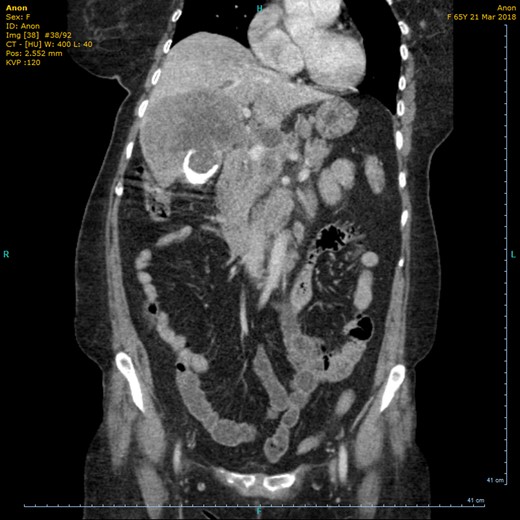

On the current admission, general examination was unremarkable and vital signs were normal. Abdominal examination revealed no organomegaly or palpable mass. Blood tests showed deranged liver function tests (ALT 45 U/l, ALP 775 U/l, total bilirubin 20umol/l, albumin 27 g/l, GGT 553 U/l), hypercalcaemia (adjusted calcium 2.73 mmol/l) and leukocytosis (WCC 10.8 × 109/l). US showed the gallbladder had poor delineation of the posterior wall and appeared large, solid and heterogenous with posterior dense shadowing and with calcific components. Where visualized, the CBD was of normal calibre and no intrahepatic duct dilatation was seen. There was a large, ill-defined heterogenous mass within the liver (Fig. 1). Subsequent computerized tomography (CT) showed a10cm solid porcelain gallbladder invading liver segments 4 and 5 (Fig. 2), with evidence of enlarged coeliac, peri-pancreatic and para-aortic lymph nodes as well as pulmonary metastatic deposits (T4 N1 M1).

US showing porcelain gallbladder with a posterior acoustic shadow.